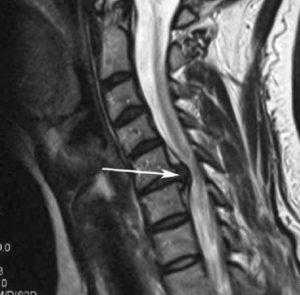

Операция при стенозе шейного отдела позвоночника

Под стенозом шейного отдела принято обозначать патологическое сужение просвета позвоночного канала, где располагается одна из главных структур ЦНС - спинной мозг. При данной патологии зачастую необходимо срочно вовлекать нейрохирургию, так как она опасна критическим неврологическим дефицитом и вегетативными расстройствами. Цервикальная стриктура может привести к ишемии головного и спинного мозга, параличу верхних конечностей (могут пострадать и ноги) и даже к парализации всей части тела ниже пораженной области.

Запущенные остеофиты шейного отдела.

Первопричиной стеноза шейного отдела в доминирующем количестве случаев является последней стадии остеохондроз, операция при спинальном сужении рекомендуется как спасение от тяжелой инвалидизации больного. Стоит заметить, что остеохондроз нами указан как обобщающее понятие, включающее широкий спектр заболеваний, которым положил начало именно данный дегенеративно-дистрофический патогенез. В группу патологий, которые развились на почве запущенного остеохондроза, относят межпозвоночные грыжи, краевые разрастания на позвонках, спондилоартроз, окостенения связок и многие другие.

Если клиника симптомов не поддается консервативной терапии или неинвазивные способы не могут быть задействованными ввиду сильно прогрессирующего стеноза, назначается операция. Вмешательство предполагает использование декомпрессионной ламинэктомии под общим наркозом. При комбинированной проблеме, например, вместе с грыжей, ее сочетают с микродискэктомией и спондилодезом. При спондилодезе осуществляют скрепление смежных позвонков металлическими фиксаторами (стержнями, пластинами, крючками и пр.), установку межтеловых имплантатов или вживление костного трансплантата с металлической гильзой.

Стеноз шейного отдела вследствие грыжевого выпячивания.